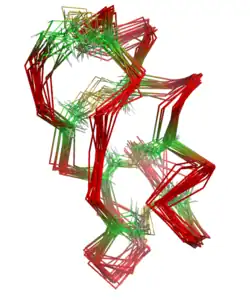

Maurotoxin is a peptide of 34 amino acids (sequence VSCTGSKDCYAPCRKQTGCPNAKCINKSCKCYGC) cross-linked by four disulfide bridges (Cys3-Cys24, Cys9-Cys29, Cys13-Cys19, Cys31-Cys34), with an atypical pattern of organization compared with other scorpion toxins; this unusual pairing of cysteine residues may be mediated by the presence of adjacent prolines. The peptide contains an alpha helix linked by two disulfide bridges to a two-stranded antiparallel beta sheet.